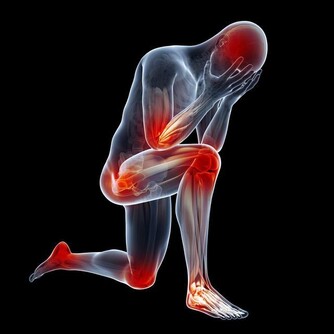

腎貯藏精氣,為人體生殖、造血、生長發育、防衛病邪的基礎物質,平衡身體水液代謝,與膀胱合作排泄尿液,負責納氣,協調呼吸運動,主骨生髓,養腦益智,促進頭髮生長,腎氣通耳,控制聽力,控制二陰的開合。

1、護好雙腳:足部保暖是養腎的一種方法,每天用熱水泡泡腳,在做一些簡單的按摩,睡覺時不要將雙腳正對空調或電扇,不要赤腳在潮濕的地方長期行走。